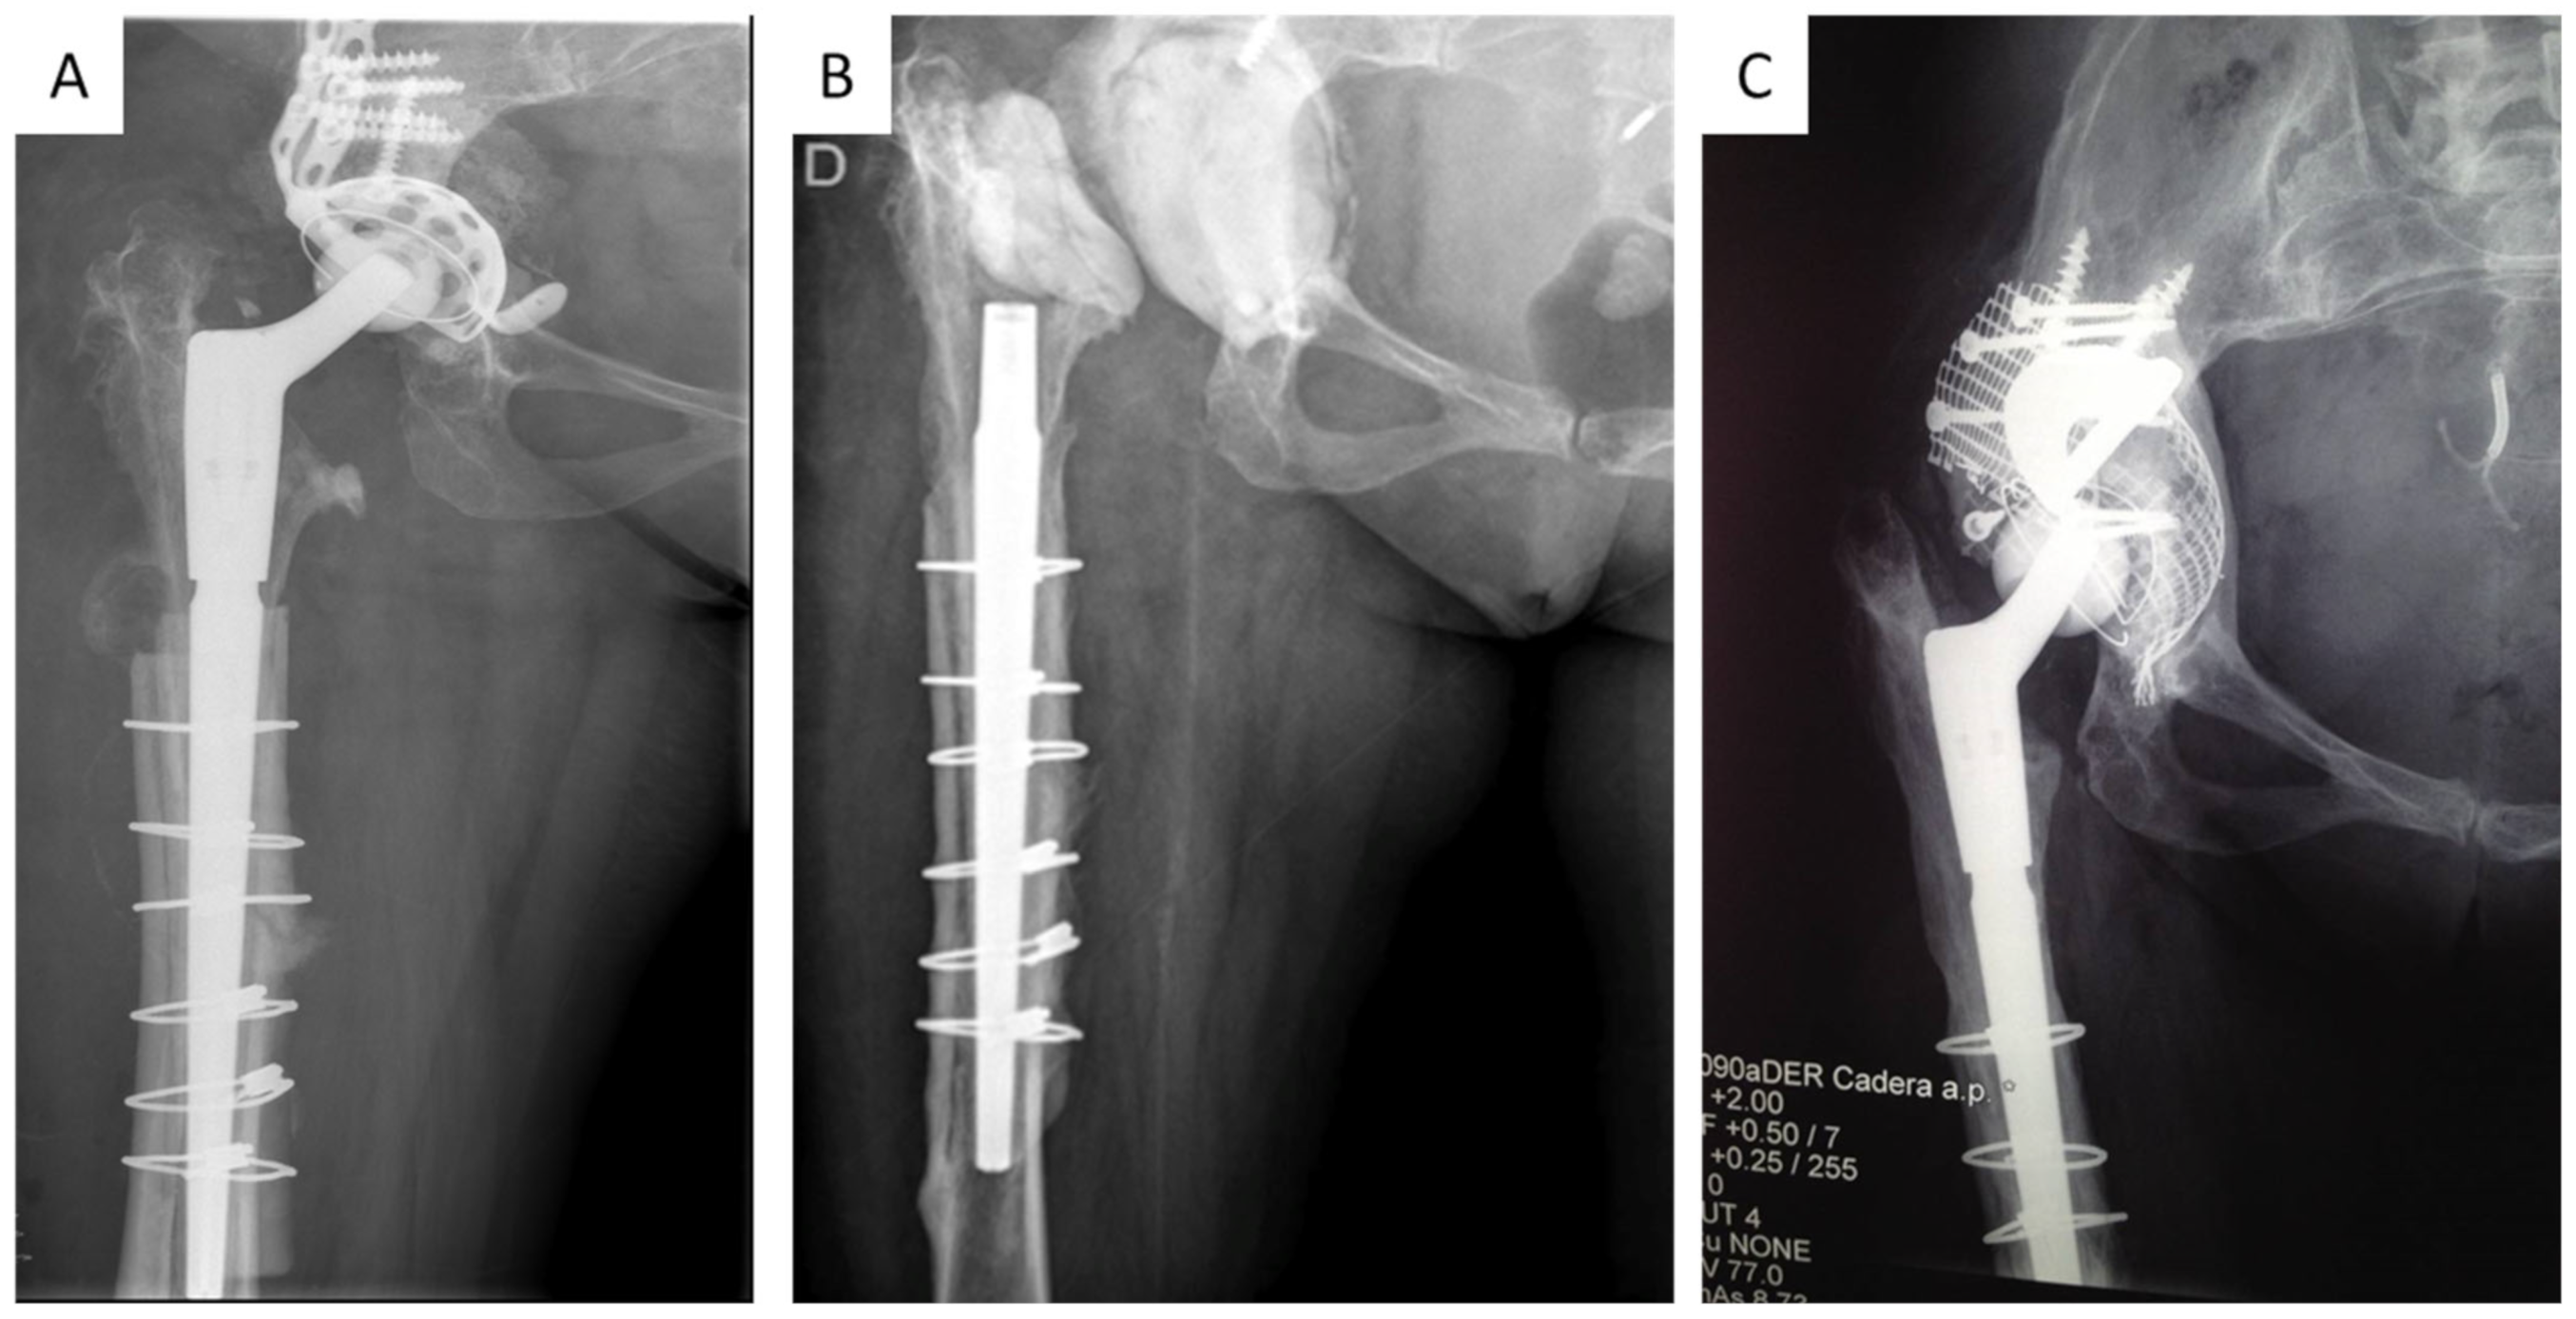

After that, a pulsatile lavage of the exposed parts of the stem was carried out using 12 L of a combined solution of saline and povidone-iodine (Betadine). Finally, an antibiotic-loaded cement spacer was placed. The use of an articulating or a non-articulating spacer was chosen based on the extent of the acetabular defect and the type of femoral stem. For severe acetabular defects and in patients with revision modular stems—following the extraction of the metaphyseal component—non-articulated spacers were used (Figure 1B).

Figure 1.

(A), Preoperative radiograph before the first stage in a patient with septic loosening of acetabular component; (B), radiograph with a non-articulated spacer; (C), radiograph at 9-year follow-up after the second stage with bone impaction grafting and trabecular metal augments (BIG-TMT).

Second-stage reconstruction was performed once all inflammatory markers were normalized or showed a downward trend two months after cessation of antibiotic treatment. During the second stage, a thorough debridement and washout was repeated. Sample collection with intraoperative pathology was performed. Once both the biopsy and Gram-stain were negative, we proceeded with the reconstruction, which was performed with varied techniques. In minor defects, an uncemented revision acetabular component was used (TMT Zimmer-Biomet). In severe defects, we used either trabecular metal augments with revision shell, cup–cage reconstruction, or a combination of trabecular metal supplements and morselized bone graft (Figure 1A–C).

The authors affirm that the human research participants provided informed consent for publication of their clinical results and also the clinical images in Figure 1A–C.